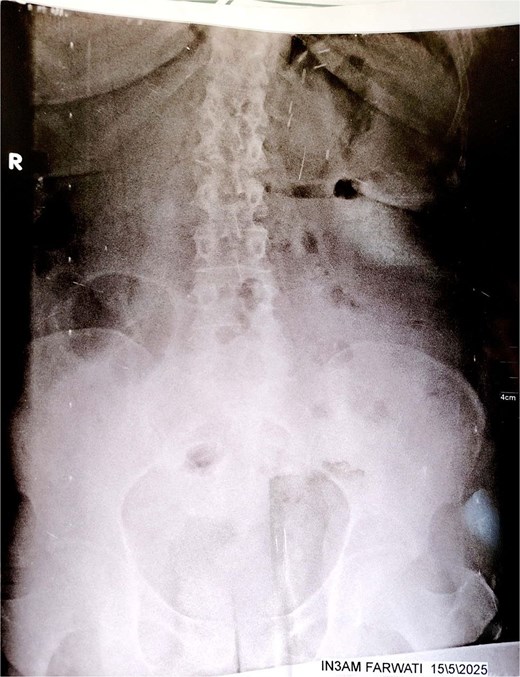

Initial imaging with a plain abdominal X-ray showed non-specific gas patterns without obstruction (Fig. 1). Contrast-enhanced CT revealed features of intestinal non-rotation, including abnormal duodenal positioning and atypical mesenteric vessel orientation. The sagittal view showed a retromesenteric duodenum without volvulus or bowel wall compromise (Fig. 2), while axial images demonstrated a reversed superior mesenteric artery (SMA)–superior mesenteric vein (SMV) relationship (Fig. 3), supporting malrotation. These findings are further illustrated in Supplementary Video S1), showing small bowel on the right, colon on the left, retromesenteric duodenum and abnormal SMA–SMV positioning. Colonoscopy showed normal mucosa without obstructive lesions.

Plain abdominal X-ray (upright position) showing prominent colonic and small bowel gas patterns with no visible air-fluid levels or signs of acute obstruction. No abnormal bowel positioning or dilation is clearly evident. These findings were non-specific and contributed to the diagnostic delay.